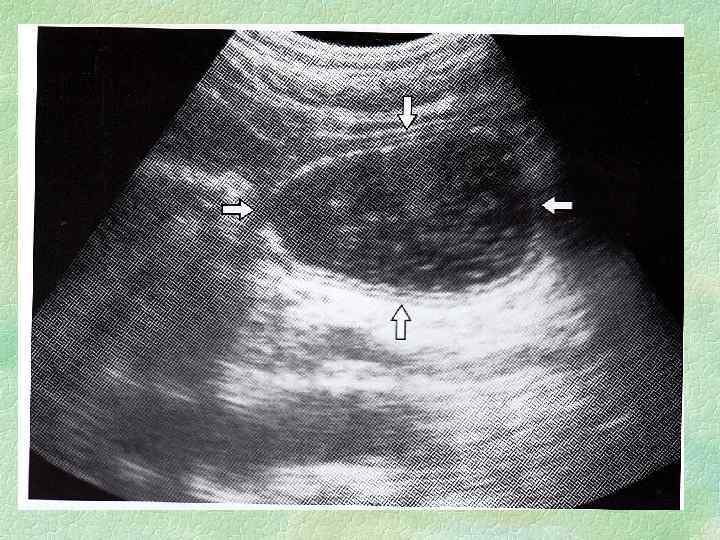

5) Лабораториялық және аспаптық зерттеулердің көріністері: 1) Ойық жараның кемшілігінің анықталуы • эндоскопиялық әдіспен қарау(98 пайыздық жағдайда )жараның орналасуының, тереңдігін , пішінін, мөлшер, н нақтылайды, жазылуын бақылауға, шырышты қабатының өзгеруіне гистологиялық бағалау жүргізуіне, малигнизацияны болдырмауга көмектеседі

• рентгенологиялық әдіспен Ниша симптомы тән, асқорыту ішек жолының маторикасының бұзылысы және қатпарлардың конвергенциясы. • 2) Хеликобактер пилориді ФГДС жасағанда асқазан денесінен және антральды бөлігінен екі биоптаттан алғанда анықталады. 3) р. Н метрия бөліктік (фракциялық)асқазанды зонтаудың көмегімен асқазанның қышқыл тнзы қызметін зерттеу жара ауруының диагнностикасында маңызды рөл атқарады. Ұлтабардың және пилорикалық каналдың ойық жарасында әдетте қышқыл өндірілуі көрсеткішінің жоғарлауы байқалды, асқазанның денесіндегі және субкардиальды бөліміндегі ойық жарада қалыпты немесе төмендеген. 4) Жалпы қан анализі ауру асқынбаған жағдайда жиі өзгермейді, гипохромды анемия жасырынды немесе айқын қан кету белгілерін көрсетеді, лейкоцитоз және ЭТЖ жылдамдауы ойық жараның пенетрациясы кезінде анықталады, 5) Нәжістің жасырын қанға оң реакциясы ойық жара ауруының асқынуы кезінде

§ Негізгі көріністері: Жаралық ойыс, қатпарлардың конвергенциясы Қосымша көріністер: Гиперперистальтика, асқазан тонусының өзгеруі, бұлшықет спазмы, пилороспазм, асқазан құрамының 12 елі ішекке эвакуациясының бұзылысы ЭФГДС: Жаралы дефект көлемі , орналасуы, қан құйылуы, бұлшық ет спазмы, пилороспазм, малигнизация, жаран ың айналасынан және түбінен биопсияға 6 -8 бөлшек алады